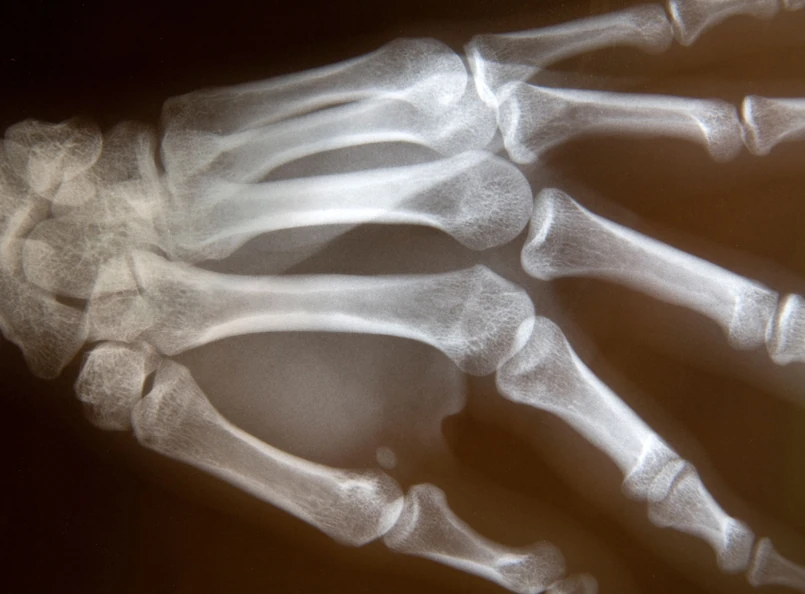

Choroba reumatyczna to wiele chorób/Shutterstock